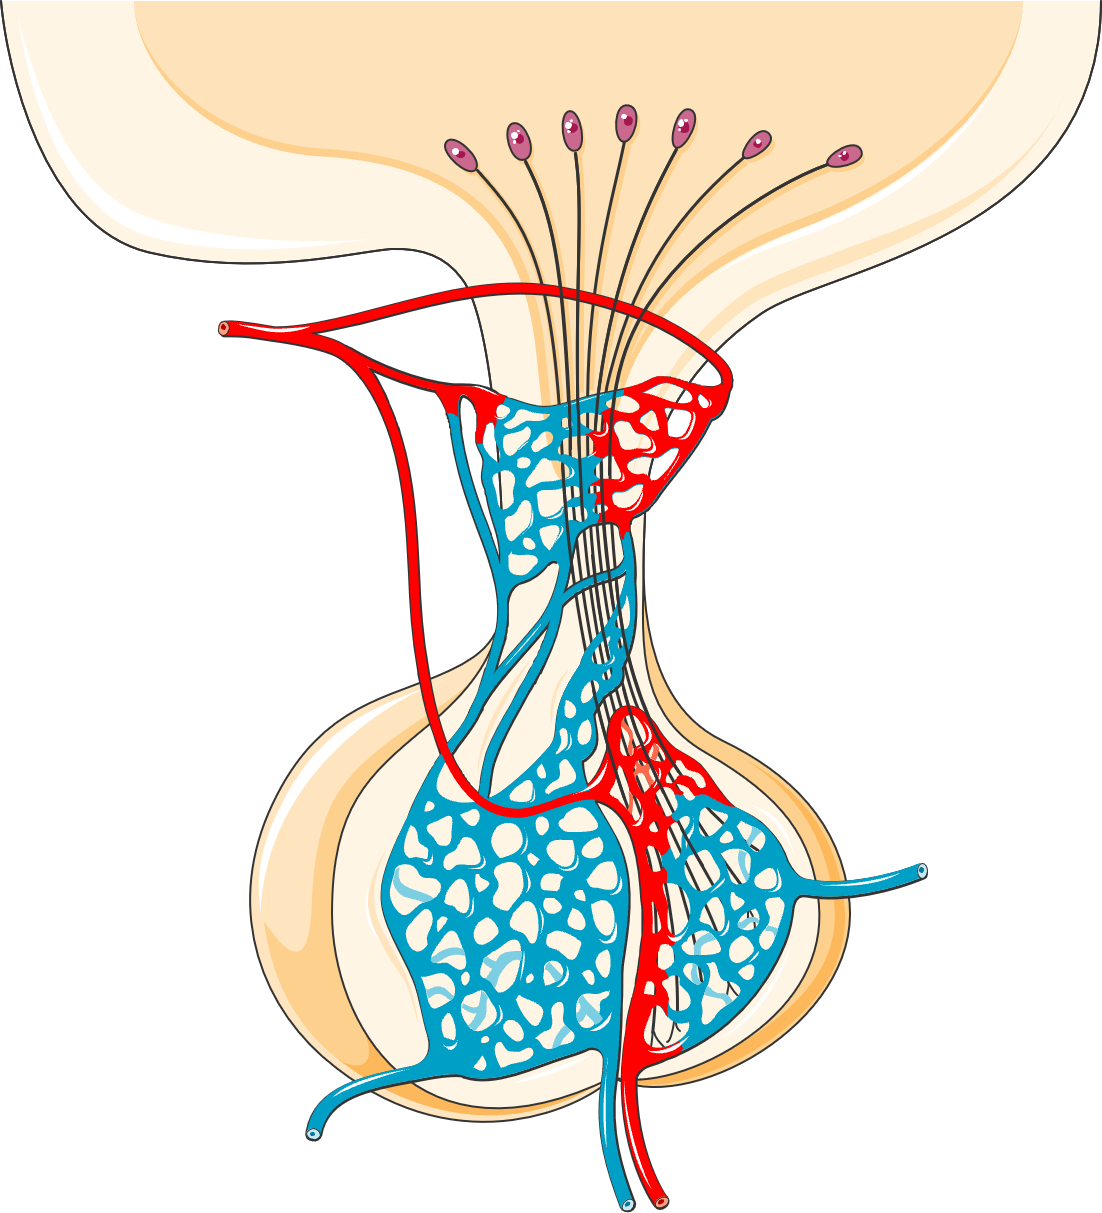

The VEGF Story: How a Tiny Clone Creates Systemic Chaos

A small clone of abnormal plasma cells — often just 5–10% of bone marrow — secretes massive amounts of vascular endothelial growth factor (VEGF) and other proinflammatory cytokines including TNF-α, IL-1β, IL-6, and TGF-β1. This single mechanism drives the full spectrum of disease.

Peripheral edema (most common), ascites, pleural effusions, pericardial effusions. Correlates with poorer survival. Often refractory to diuretics until the clone is treated.

- Cytokine-mediated: IL-1β, IL-6, TNF-α, and VEGF drive pulmonary vascular remodeling

Not in diagnostic criteria but commonly seen on biopsy. Typical pathology includes MPGN-like lesions, mesangiolytic glomerulonephritis, or thrombotic microangiopathy. Electron microscopy shows glomerular microangiopathy with endothelial injury — the same endothelial damage found in nerve vasa nervorum, suggesting generalized endothelial injury is a unifying mechanism.